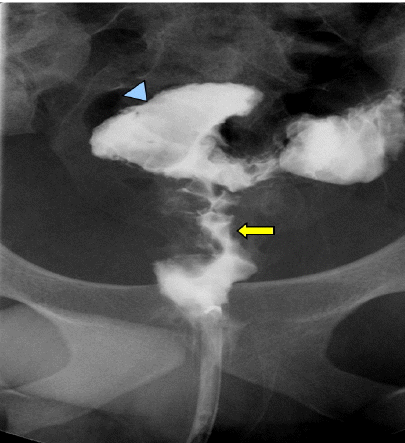

내시경 및 위장관 영상 소견: S상결장 검사에서 직장 S상결장 접합부위 협착 및 1시 방향으로 큰 궤양과 황갈색 삼출물 소견(Fig. 2)이 보였다. 바륨검사에서는 협착부 위로 커다란 궤양이 보였으며, 협착부 아래로는 허혈성 장염에서 보이는 엄지손가락으로 눌린 듯한 모양(thumb-printing)이 보였다(Fig. 3). 그러나 크론병을 시사하는 선상 궤양, 장간막면의 단축 등의 소견은 없었다.

Figure 3.

A barium study shows a large ulcer (arrowhead) and thumb printing (arrow) at the rectosigmoid junction.